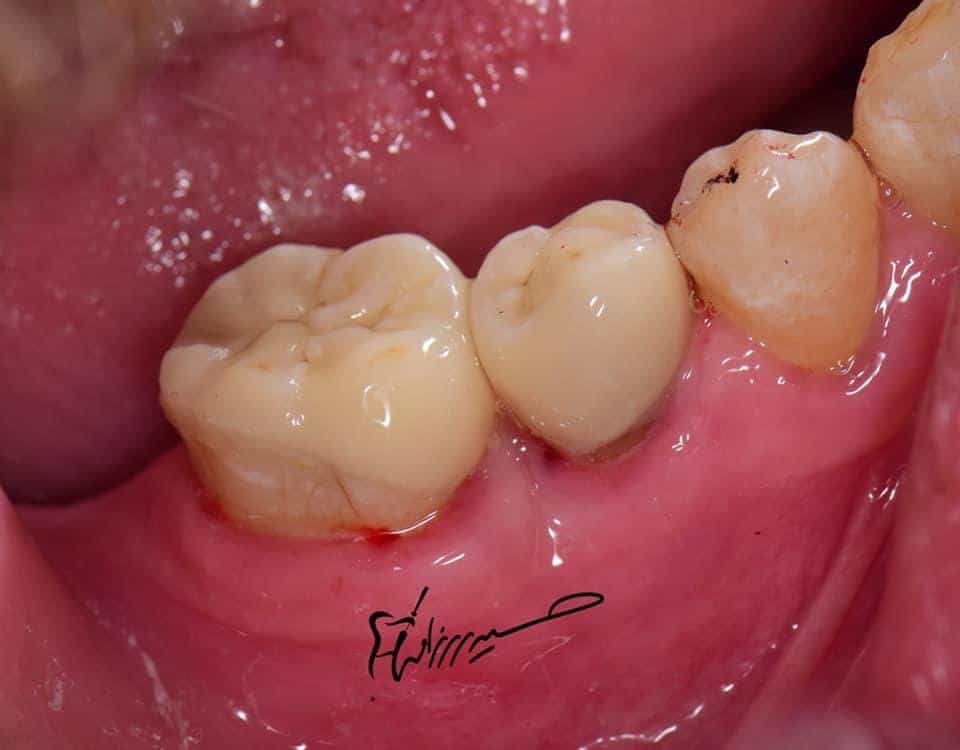

Final situation

Lateral view

Before and after